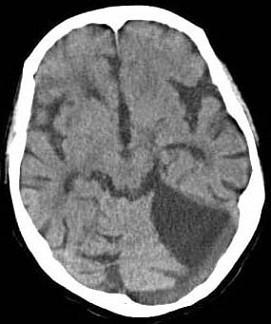

问题 头颅MRI?TWI出现如图所示脑梗死,该病灶是下列哪两条血管供血区之间边缘带的局部缺血()

选项 A.大脑前动脉和大脑后动脉 B.大脑中动脉的深穿支和大脑中动脉的皮层支 C.大脑中动脉和大脑后动脉 D.大脑中动脉和大脑前动脉 E.大脑后动脉和小脑上动脉

答案 C